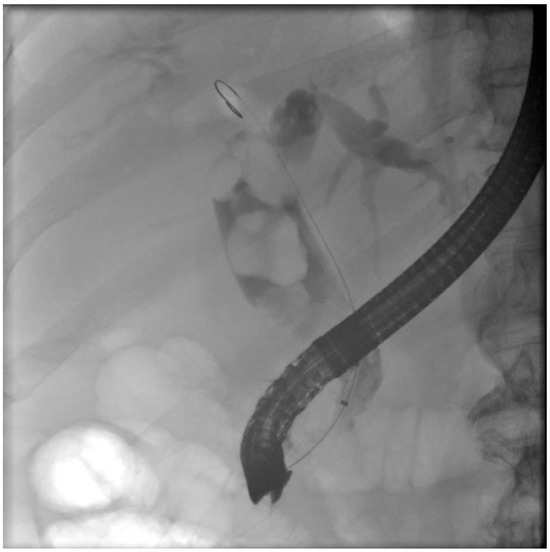

- Ierardi, A.M.; Rodà, G.M.; Di Meglio, L.; Pellegrino, G.; Cantù, P.; Dondossola, D.; Rossi, G.; Carrafiello, G. Percutaneous Transhepatic Electrohydraulic Lithotripsy for the Treatment of Difficult Bile Stones. J. Clin. Med. 2021, 10, 1372. [Google Scholar] [CrossRef] [PubMed]